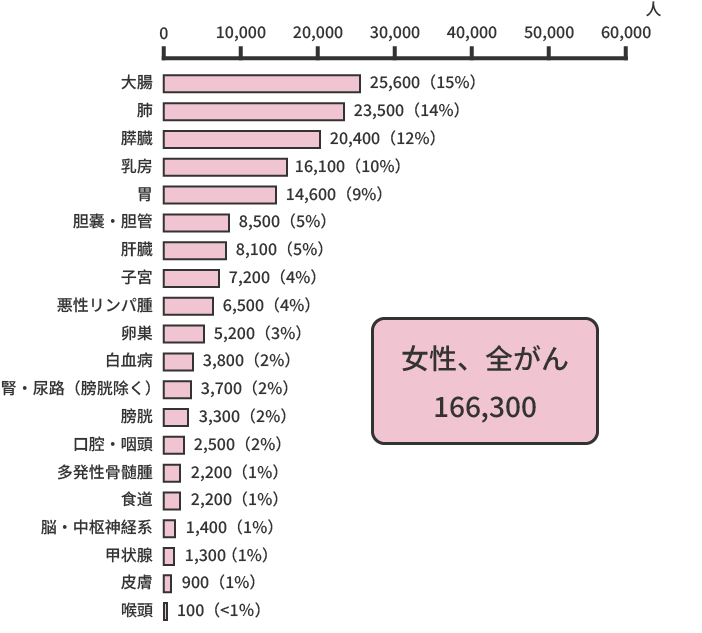

2021年の推計値では、日本のがん患者数は、約100万9,800人(男性約57万7,900人、女性約43万1,900人)です。部位別でみると、男性では前立腺がん(17%)、胃がん(16%)、大腸がん(15%)、肺がん(15%)、肝臓がん(5%)の順で多く、女性では乳がん(22%)、大腸がん(16%)、肺がん(10%)、胃がん(9%)、子宮がん(7%)の順で多くなっています。

また、同じく2021年のデータによると、がんによる死亡者の数は、約37万8,600人(男性約21万8,900人、女性約15万9,700人)と推計されています。部位別でみると、男性では肺がん(24%)が最も多く、次いで大腸がん(13%)、胃がん(12%)、膵臓がん(8%)、肝臓がん(7%)の順、女性では大腸がん(16%)が最も多く、肺がん(14%)、膵臓がん(12%)、乳がん(10%)、胃がん(9%)と続きます。

部位別予測がん罹患数(2021年)